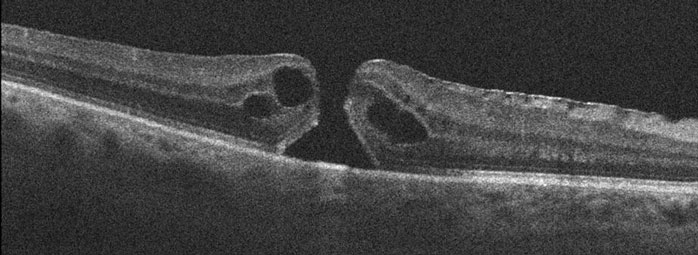

A macular hole consists of a small, round defect in the central macula, the part of the retina we use for our straight-ahead vision. The hole is thought to be caused by the vitreous pulling on the central macula, creating a central defect in the retinal tissue. It usually occurs for no obvious reason (idiopathic), although a macular hole can also be caused by trauma or retinal detachment. Macular holes are most common in women in their early 60’s and are not associated with any systemic medical problems. Approximately 10% of patients with a macular hole in one eye will eventually develop a macular hole in the other eye.

You can’t diagnose a macular hole by looking in the mirror since your eye will usually look and feel normal. The diagnosis is made with a thorough retinal examination through a dilated pupil. Early stages of macular hole formation are often difficult to diagnose, often requiring additional testing such as OCT scanning which offers a near microscopic macular image.